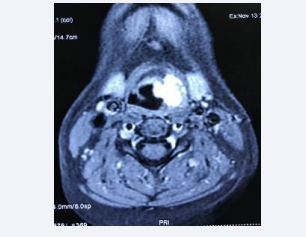

Magnetic resonance imaging (MRI) of the neck revealed a neoplastic lesion in the glottis and supraglottis, more notably on the left, with obliteration of the pyriform sinus and ipsilateral vallecula; anterior commissure and vocal folds bilaterally. No nodular lesions were found in the neck (Figures 4-6).

Axial MRI image showing hemangioma in the left vocal fold

Figure 4: Axial MRI image showing hemangioma in the left vocal fold